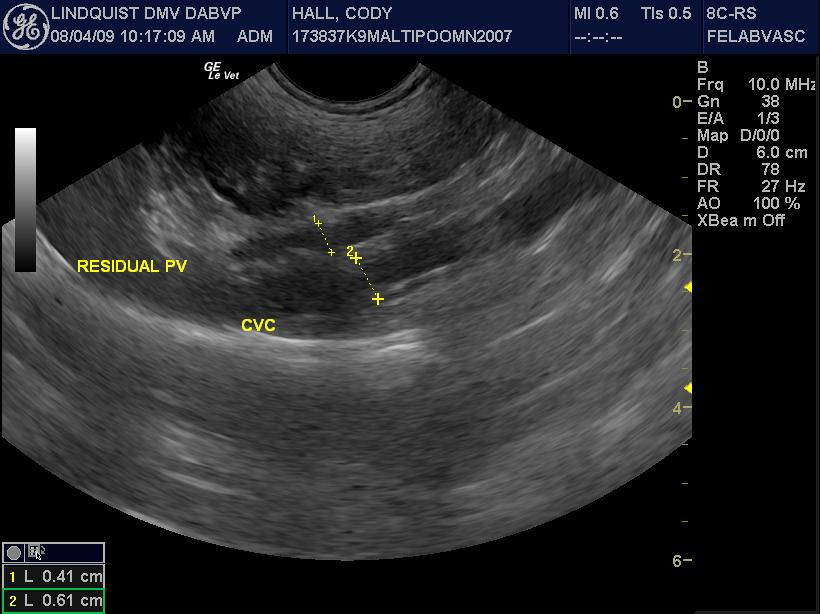

A 2-year-old MN Malti-poo was presented for recheck examination after being evaluated at an emergency facility for anorexia, diarrhea, and a pruritic face. Abnormalities on blood work at the emergency facility were elevated ALT activity and bilirubinuria. Physical examination was unremarkable. CBC and blood chemistry showed leukocytosis, neutrophilia, monocytosis, elevated BUN, high BUN/Creatinine ratio, and mild hypocalcemia. Urinalysis was normal. Urine culture yielded no growth.